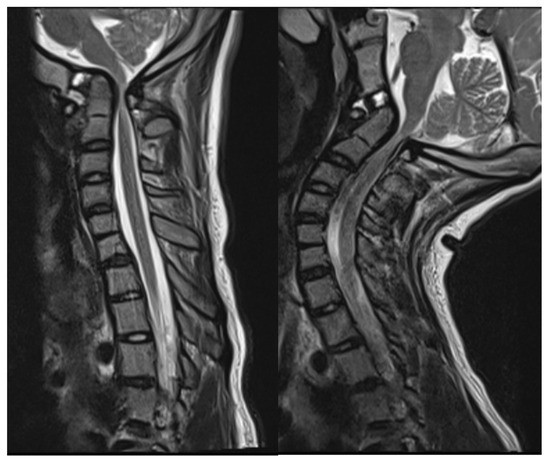

2.2. Imaging and Diagnosis

4. Results